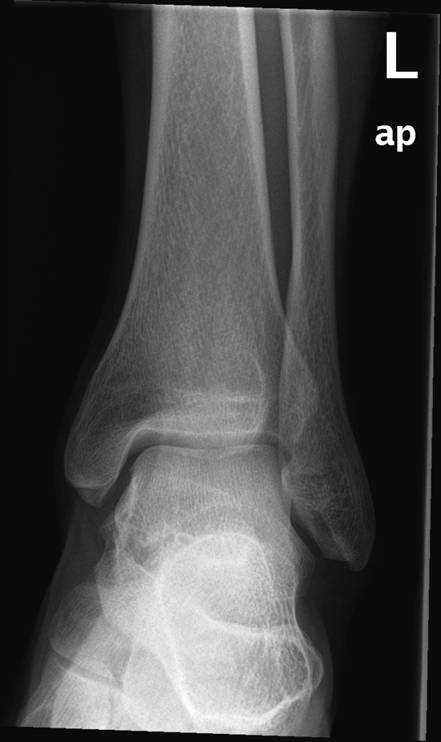

Fodled (2 projektioner), normal, røntgen

Normalt røntgenbillede af venstre fodled i 2 projektioner